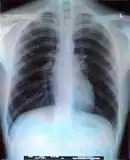

An X-Ray picture of the Human Body, more specifically, the rib cage.